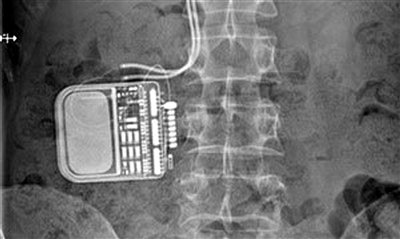

另类疗法——

植入电极以电镇痛

由于患有一种严重的丛集性头痛,每隔一段时间就会发作,荷兰人桑德·佩里杰决定将一个神经刺激装置植入身体。

当头痛发作的时候,通过遥控器,该装置能向其头部神经发出电脉冲,起到舒缓头痛的作用。如此大胆另类的疗法实在让人后背发凉,但据称该植入装置非但没有达到预期效果,还为佩里杰带来了意想不到的心理问题,实在是得不偿失。